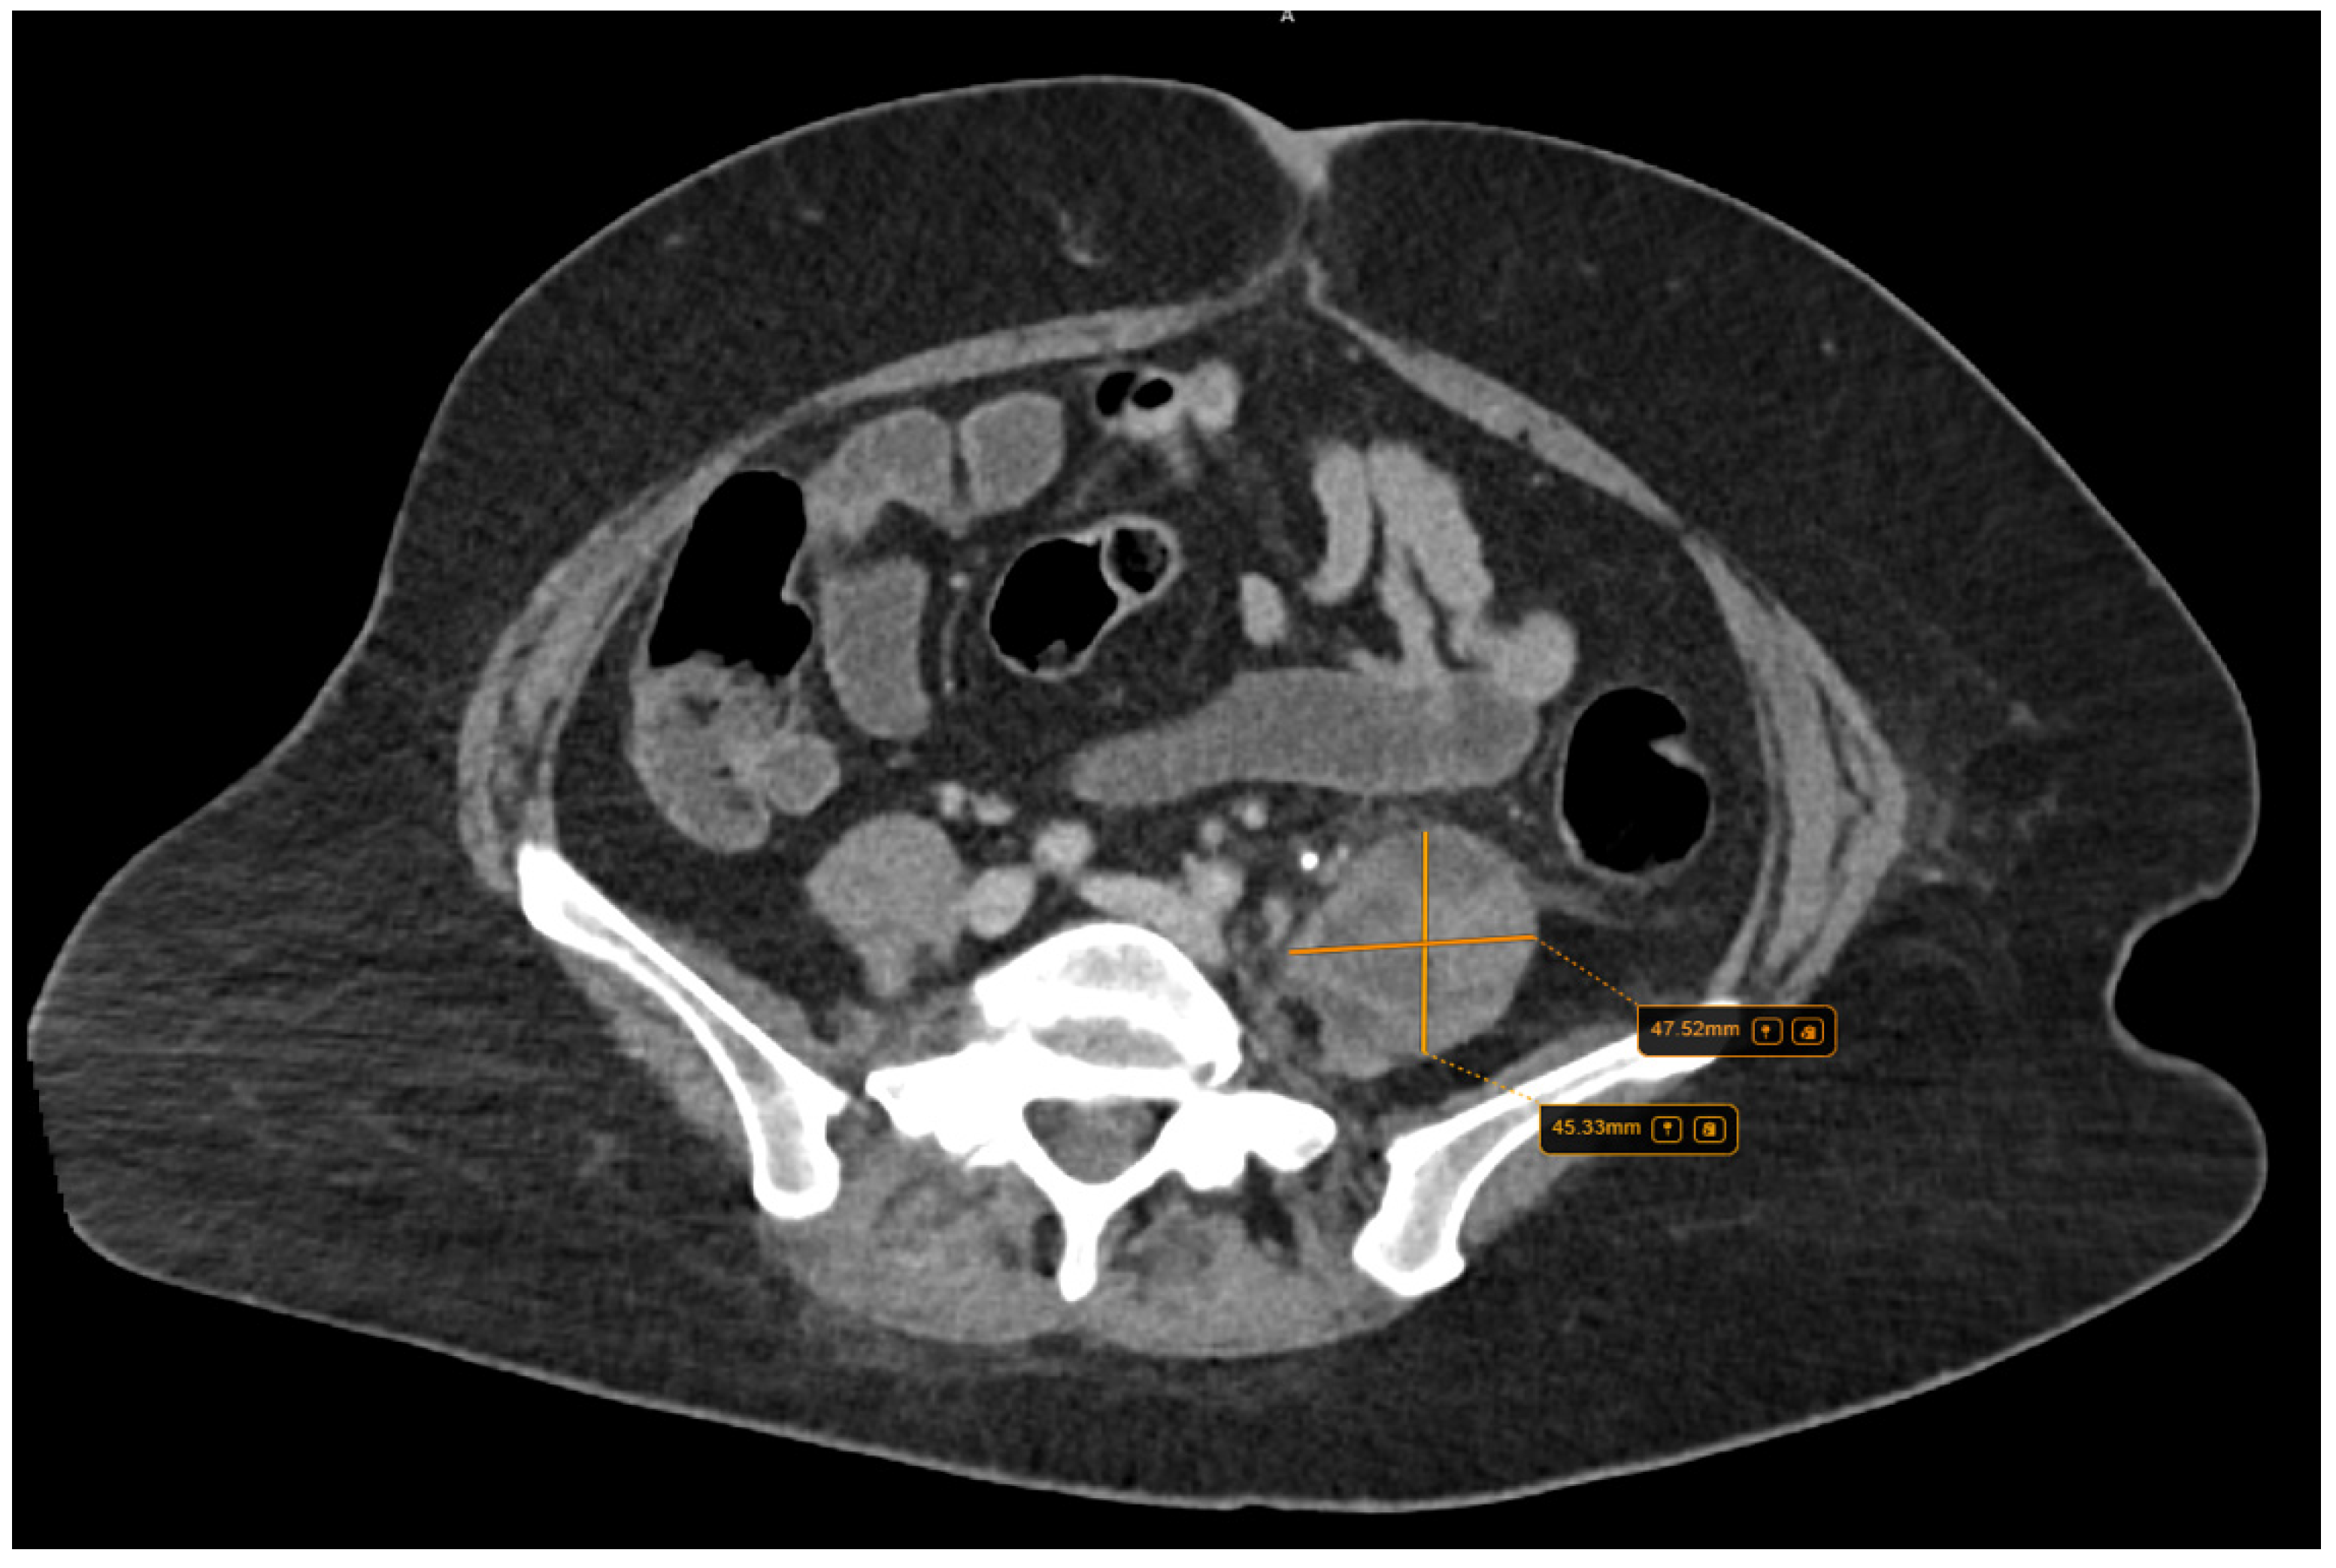

Further, the abdominal and pelvis CT scan with contrast substance showed the cholelithiasis observed on abdominal ultrasound with common bile duct diameter in normal limit values and fused abscess-type collections at the interfibrillar level of the left iliopsoas muscle. The CT also shows hepatomegaly with cranio-caudal dimensions of the right hepatic lobe of 220 mm, a clear, regular outline, a homogeneous structure, and a cholecyst with multiple calculi up to 17 mm (Figure 3).

Figure 3.

Collections of fused abscesses at the interfibrillar level of the left psoas muscle that cause volumetric growth (4.53/4.75 cm) compared to the contralateral side and associate densifications in the adjacent fatty tissue.